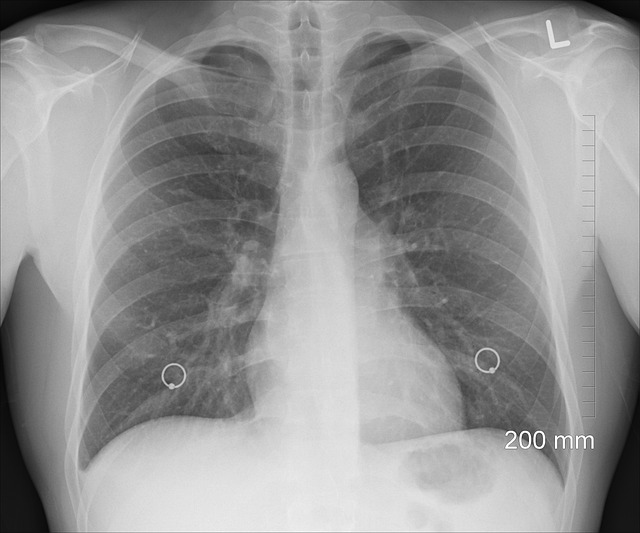

Chest X-ray or CT Scan: To look for emphysema or rule out other lung problems/heart failure.